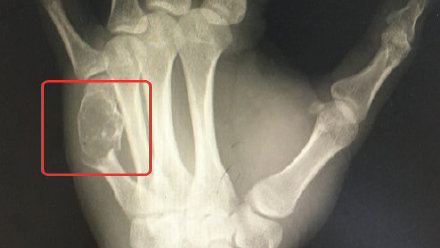

但是最近手疼的实在受不了,最后完全不能动弹,这个时候他才意识到问题的严重性,慌忙去医院检查,这不查不知道,一查吓一跳,医生表示手疼是因为有内生性软骨瘤,这个瘤已经将正常的骨头都‘融’成‘豆腐渣’。

不过,医生也表示,这个瘤属于良性瘤,属于慢性病,生长很缓慢,一般在骨折后才能发现,这次黄先生的如此病症,也是由于工作强度和持久度导致的。因为及时就医,黄先生做了一个小手术,目前已经在恢复中。